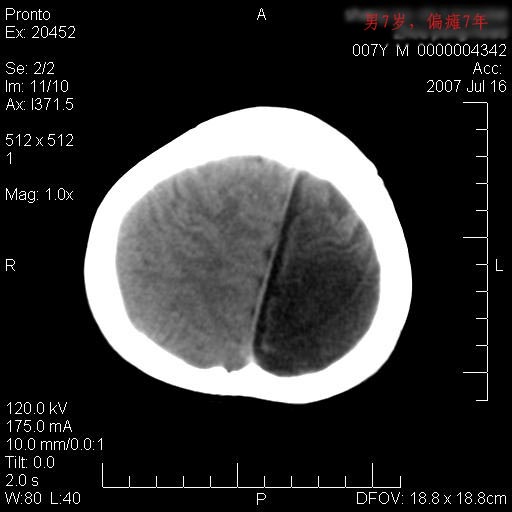

男性 7岁:偏瘫7年,出生时脑内出血。

左侧脑叶体积缩小。密度减低,左侧脑室牵拉扩大并向左移位,左侧脑室颞角与侧裂池相通并呈囊性扩张。考虑左侧大脑发育不全,软化灶并穿通畸形。

左侧颅腔变小,左侧大脑半球体积缩小密度减低,呈负占位效应,左侧侧脑室扩大,出生时有脑出血病史。多考虑先天因素,左侧大脑前、中动脉起始部狭窄或闭塞,即烟雾病可能性大。